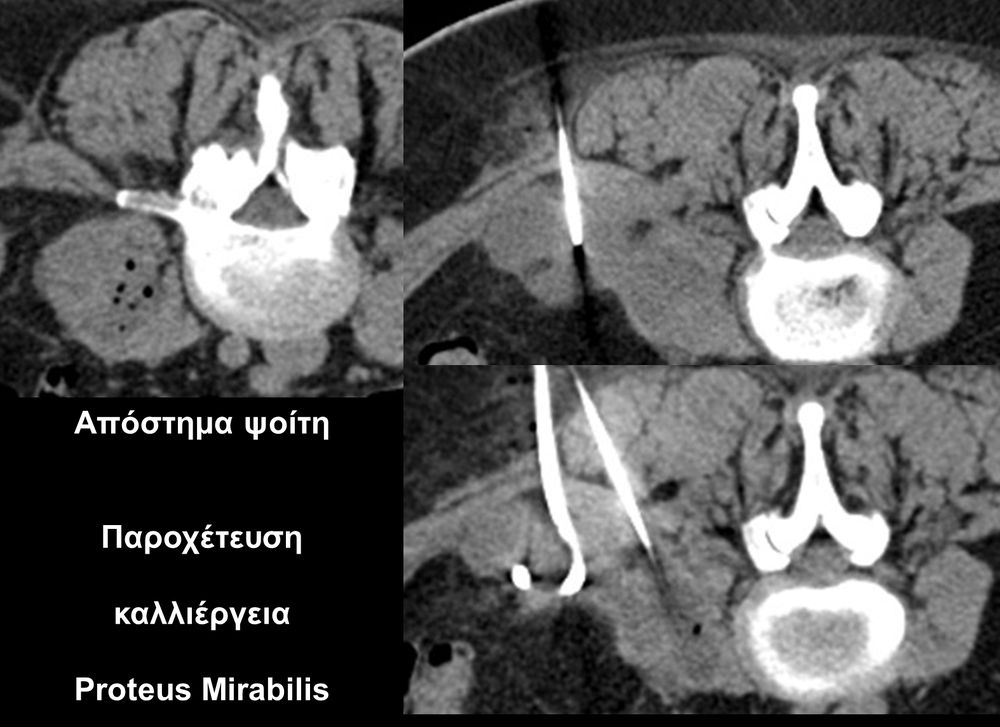

Η οστική βιοψία και η βιοψία όγκων μαλακών μορίων χρησιμοποιείται για την ιστολογική διάγνωση αλλοιώσεων (καλοήθων - κακοήθων / πρωτοπαθών ή μεταστατικών) ή για τη λήψη υλικού προς καλλιέργεια ώστε να αναδειχθεί το μικρόβιο που προκαλεί τη λοίμωξη του μυοσκελετικού συστηματος (πχ σπονδυλοδισκίτιδα). Η βιοψία υπό συνεχή απεικονιστική καθοδήγηση συμβάλλει στην υψηλή ακρίβεια τοποθέτησης της βελόνης εντός της βλάβης με ασφαλή προσπέλαση. Η χρήση σύγχρονων ομοαξονικών συστημάτων βιοψίας (coaxialtechnique) επιτρέπει την λήψη πολλαπλών δειγμάτων με μια μόνο παρακέντηση.